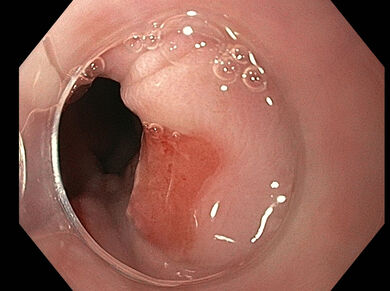

Die 23-jährige Patientin wird vom Notarzt nach selbst beigefügten Schnittverletzungen am Hals und verschluckter Rasierklinge eingeliefert. Bezüglich des Abdomens wurden keine Beschwerden angegeben. Das Röntgenbild zeigt eine halbe Rasierklinge in Projektion auf den Magen ohne freie Luft. Bei nüchterner Patientin erfolgt die ÖGD unter Sedierung. Hier zeigt sich die Radierklinge im Corpus. Was nun